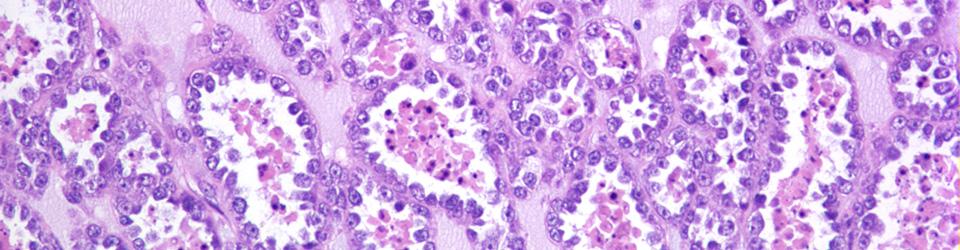

banner image

Biobanks play a crucial role in modern research by providing a wealth of biological samples and data that can be used to enhance scientific inquiry. They offer a range of sample collections, from large national databases to bespoke collections, which can significantly boost research efforts. Biobanks are essential for creating biobanks, validating results, and addressing the challenges of data security and legalities in shipping biological materials. They also help researchers identify biomarkers for diseases and contribute to personalized medicine by providing valuable resources for complex diseases like cardiovascular disease, cancer, and diabetes. Biobanks are vital for improving population health and making medicine more effective and customized for each individual.